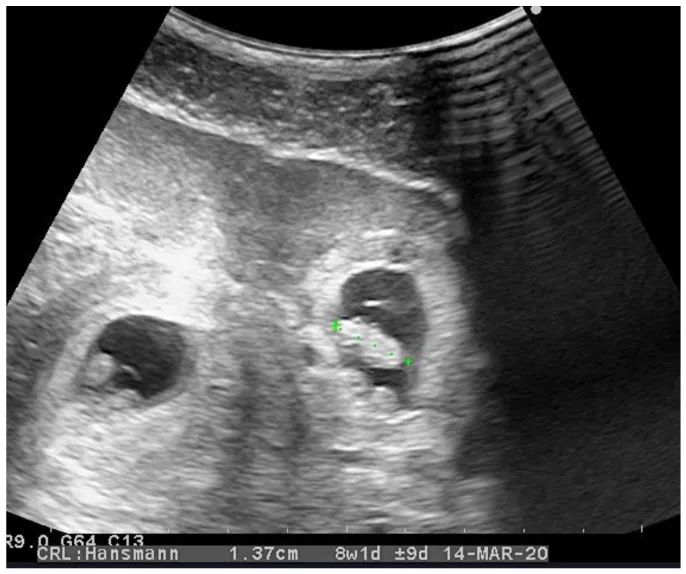

有一篇文獻報道了一例異位聯合妊娠的情況,這名立陶宛的28歲女性在懷孕第7周的時候發生腹痛,到醫院檢查發現存在異位聯合妊娠。

經陰道超聲可見宮內妊娠(左)和輸卵管異位妊娠(右)